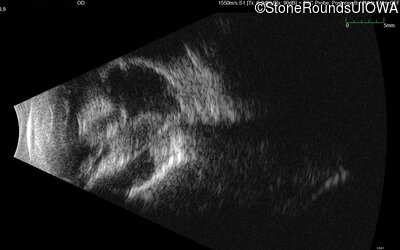

B-Scan Ultrasonography - Right - No Light Perception